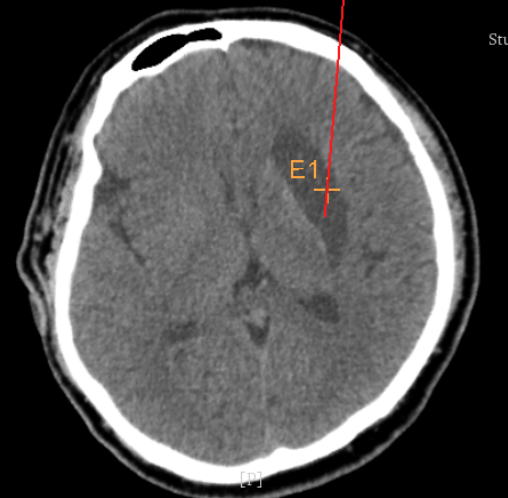

術(shù)前CT:血腫已經(jīng)液化,但仍有占位效應